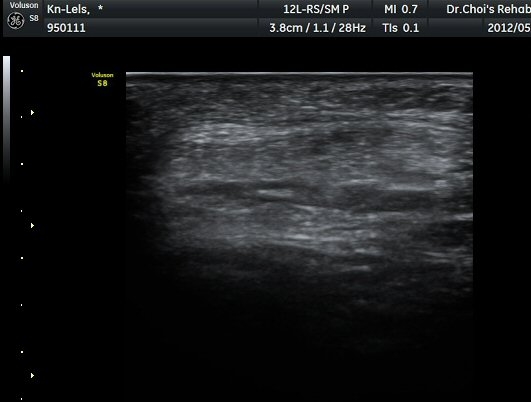

½½°³°ñ¾Æ·¡ ÈûÁÙ Á¾´Ü¸é°Ë»ç¿Í Ⱦ´Ü¸é°Ë»ç¿¡¼­ ÈûÁÙÀÇ ºñÈİ¡ °üÂûµÇ°í(±×¸² 3, 4).